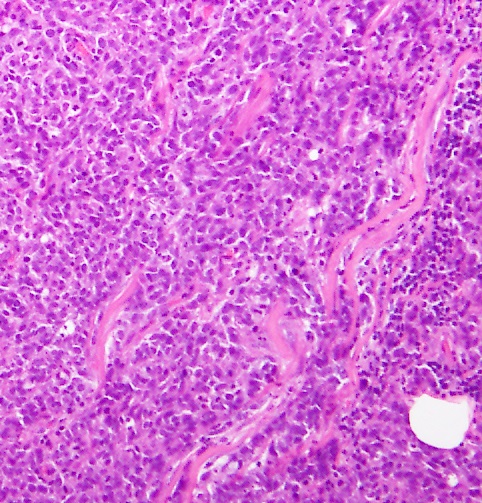

トリプルネガティブ乳がんの免疫染色パターン ER(-) PgR(-) HER2(-) 高Ki67

トリプルネガティブ乳がんはがんのグレードが高く、多くはグレード3です。また多くがベーサル様細胞(これは乳管の基底膜細胞様という意味)と言われており、ベーサルタイプ乳がんは進行が早く、より悪性度が高い乳がんです。ベーサルタイプの乳がんの多くが、トリプルネガティブ乳がんで、またトリプルネガティブ乳がんの多くがベーサルタイプという関係になっています。

トリプルネガティブ乳がん(TNBC)は、乳がん全体の15%程度を占めています。TNBCは、エストロゲンとプロゲステロンの受容体の免疫組織化学(IHC)による発現が1%以下で、HER2の過剰発現や増幅がないことが標準的な定義となっています。さらに、TNBCは通常、組織学的悪性度、増殖能が高く、増殖し、多くの壊死組織を伴っています。このタイプのがんは、40歳未満の女性、アフリカ系、ラテン系の女性、またはBRCA遺伝子(主にBRCA1遺伝子)の変異を有する女性に多く見られます。

基底様TNBCは、全TNBCの約70-80%を占め、分子レベルで他の乳がんとは異なる特徴を持っています。基底様TNBCは、通常高い細胞増殖能を示し、Ki-67という増殖指標も高値を示します。さらに、p53遺伝子の変異が高頻度で認められ、DNA修復機構に関与するBRCA1遺伝子の欠失や変異がある場合も多いです。これらの遺伝子変異は、細胞の分裂や増殖の異常を引き起こし、がんの進展に寄与すると考えられています。